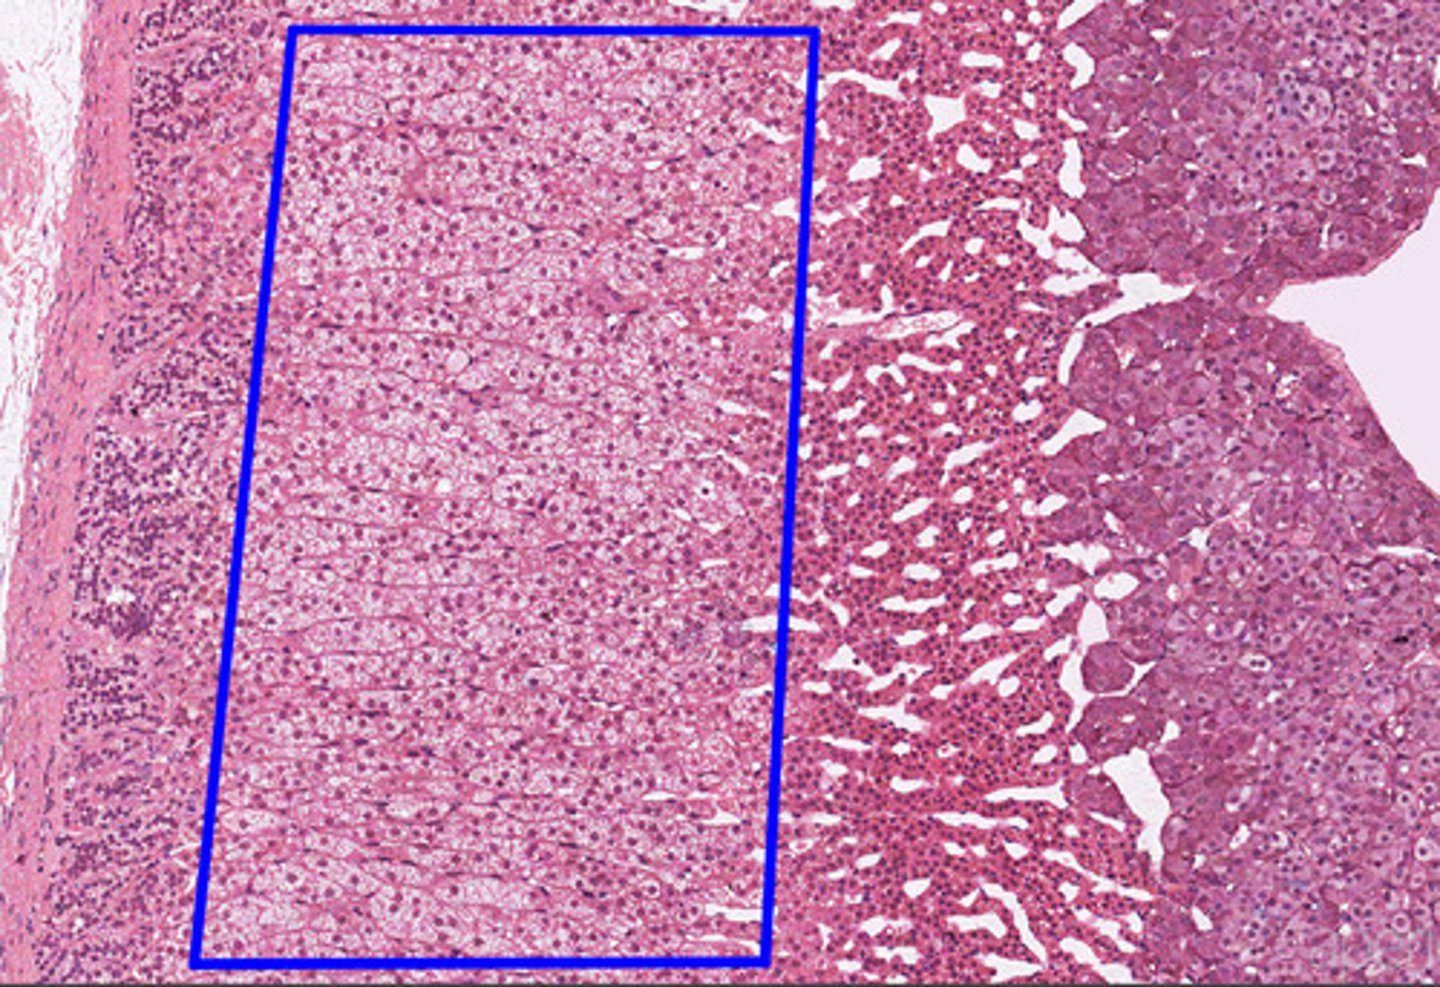

Adrenal gland

Adrenal cortex

Zona glomerulosa

Zona fasciculata

Zona reticularis

Adrenal medulla